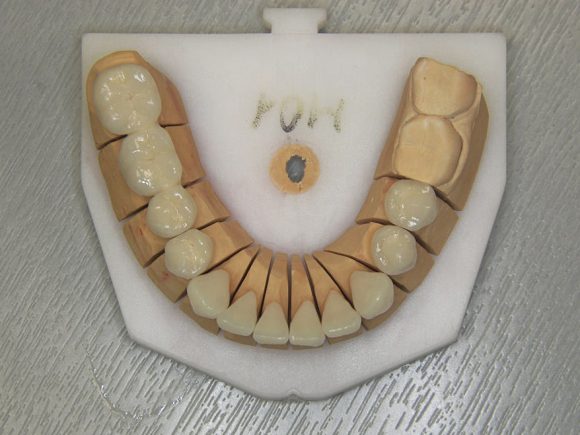

Implantátumok már a gyógyulás után, a foghíd pótlások készítése során. Az implantátumok ún. implantátum felépítményeket kapnak, mely a készülő porcelán koronák csonkját képezik, erre próbáljuk fel a foghíd vagy korona fog vázát.